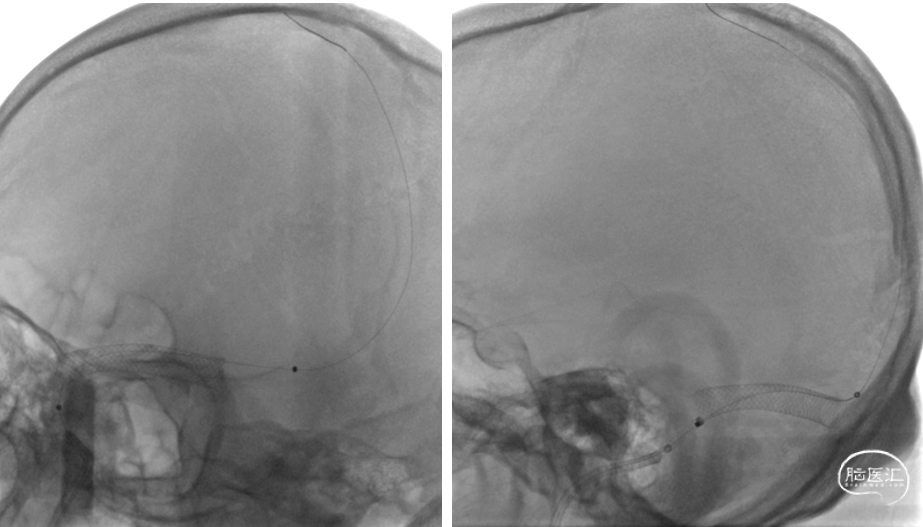

右侧颈总动脉造影示:上矢状窦显影模糊,右侧横窦、乙状窦未见显影,静脉回流缓慢。穿刺右侧颈静脉,留置8F血管鞘,全身肝素化,50万尿激酶入动脉滴注。

在泥鳅导丝导引下将8FGuiding内衬多功能导管,置于上矢状窦,反复负压抽吸可见抽出大量暗红色血栓,手推造影,静脉回流缓慢,上矢状窦仍显影欠佳,在泥鳅导丝导引下将6FNavien中间导管送至右侧横窦时推进困难,撤出中间导管。

在泥鳅导丝导引下将8FGuiding内衬多功能导管,置于上矢状窦

以8FGuiding反复负压抽吸,可见抽出大量暗红色血栓

手推造影,静脉回流缓慢,上矢状窦仍显影欠佳